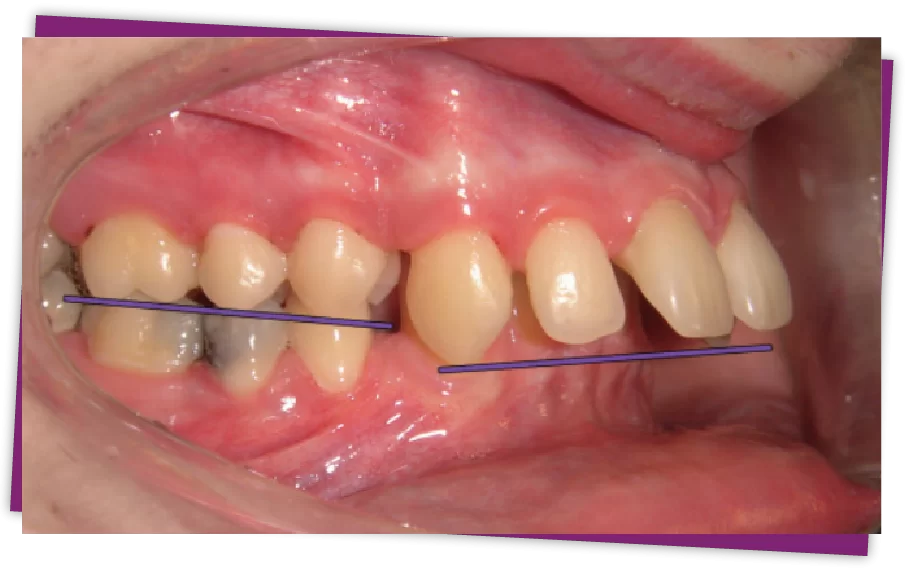

Răng hô hay còn được gọi với những tên khác là răng vẩu, răng vổ, cắn hô vẩu, khớp cắn hạng 2. Hô là tình trạng bệnh lý về hàm mặt thường gặp ở khá nhiều người.

Đây là một trong những dạng sai lệch khớp cắn mà trong đó tương quan hai hàm răng trên dưới không đạt chuẩn tỷ lệ, hàm trên đưa ra quá mức so với hàm dưới.

Khi nghĩ đến các biện pháp khắc phục tình trạng hô, người ta thường nghĩ đến phương pháp niềng răng, tuy nhiên niềng răng chỉ có tác dụng với trường hợp hô do răng (loại 1 và 3), riêng với trường hợp hô do hàm thì niềng răng không hoặc rất khó có thể giải quyết được.